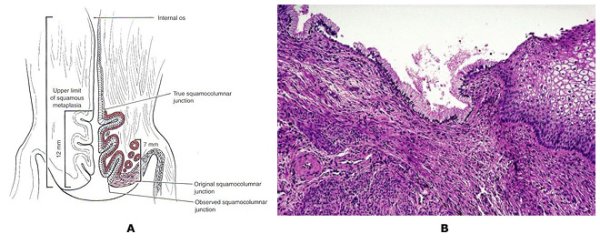

Анатомия и гистология шейки матки

Эпителий шейки матки гистология строение